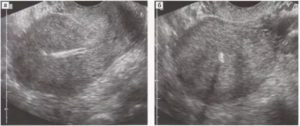

Анэхогенные образования в яичнике выглядят на мониторе как темные пятна различной формы и размеров. Такое пятно может быть единственным, их может быть несколько.

Анэхогенное образование в левом яичнике – это круглая киста, имеющая однородную структуру и четкий контур.

Медицинское заключение «анэхогенное образование в левом или правом яичнике» женщина получает на руки после того, как по различным причинам прошла процедуру ультразвукового обследования внутренних половых органов или малого таза.

Следует понимать, что анэхогенное или гипоэхогенное образование в левом яичнике – это патология, которая не является диагнозом.

Это описание того, каким образом произошло отражение луча ультразвука от яичника: оборудование излучает ультразвуковые волны, ткани и органы человека их либо пропускают неизмененными (анэхогенные или эхонегативные органы и образования), либо отражают в той или иной степени. Анэхогенная структура является той, в которой содержится жидкость.

В случае с яичником подобное заключение УЗИ малого таза значит, что врач-сонолог диагностирует кисту. Последующие действия женщины по получении подобных данных о своем здоровье – посещение врача-гинеколога, поскольку кисты могут быть абсолютно разными, и терапия у них различается значительно.

Анэхогенное образование – киста яичника – являет собой одиночное овоидное включение круглой или овальной формы, с утолщенными стенками. Анэхогенная структура обязана содержать жидкость, к ней может добавляться кровь.